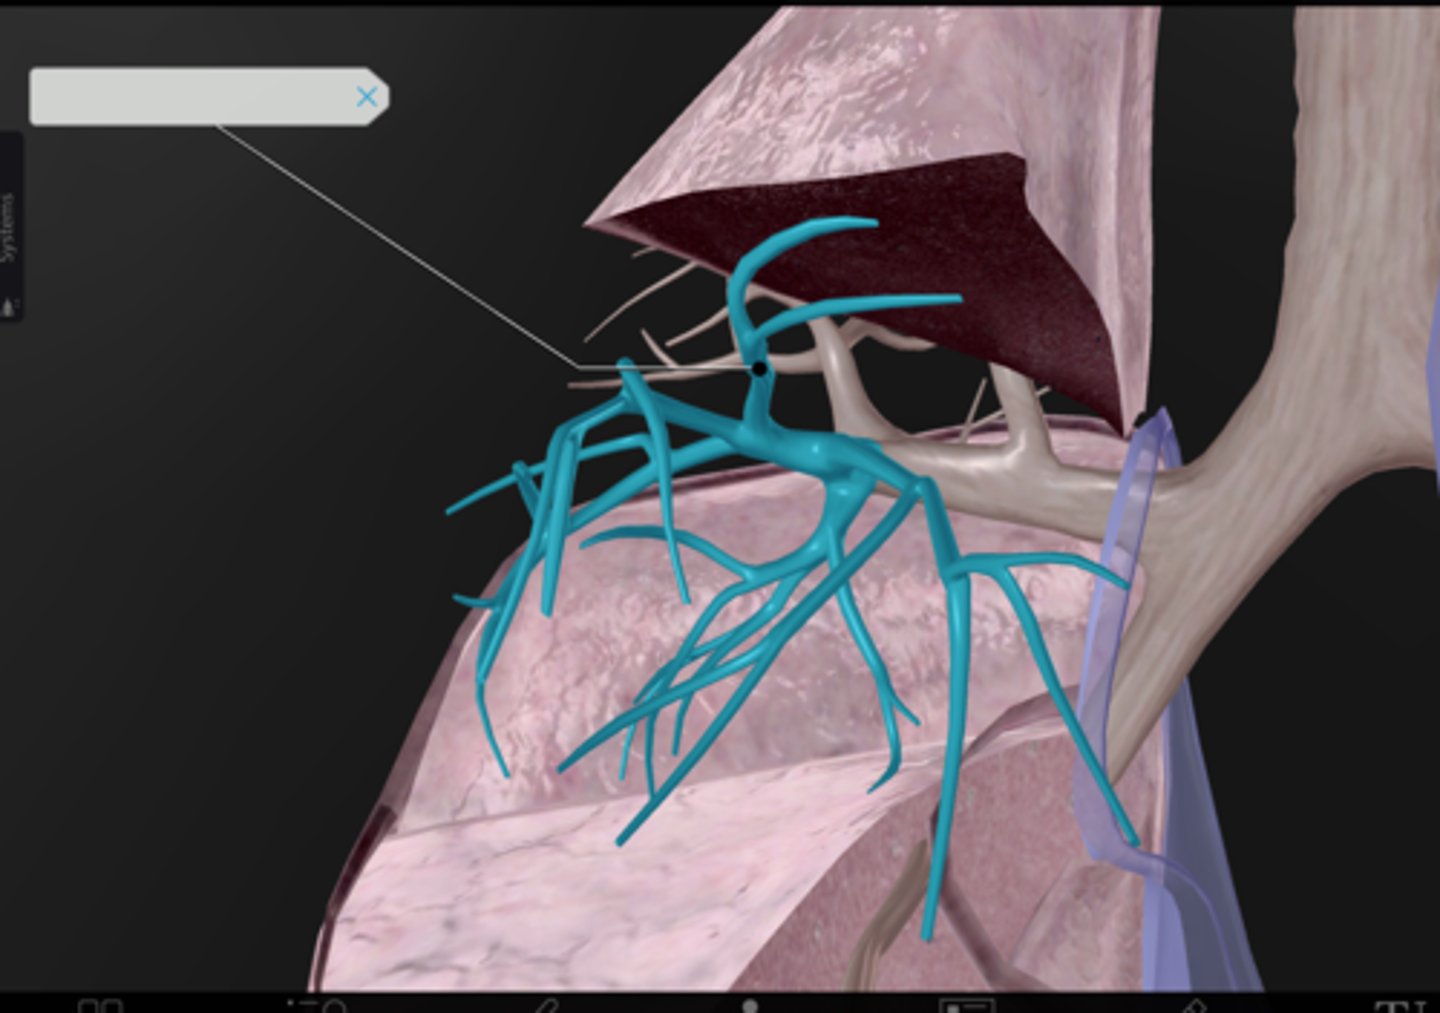

Pulmonary arteries

Pulmonary veins